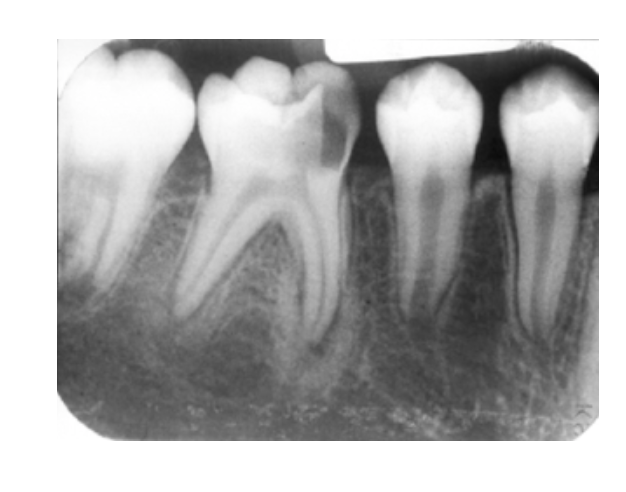

Periapical Cemento-Osseous Dysplasia (PCOD)

Reactive Process

* Unknown Origin

Most common:

* apices of mandibular anteriors

* Middled aged black females

* Vital Teeth

Starts RL–>progress to RO (w/RL halo) as it matures